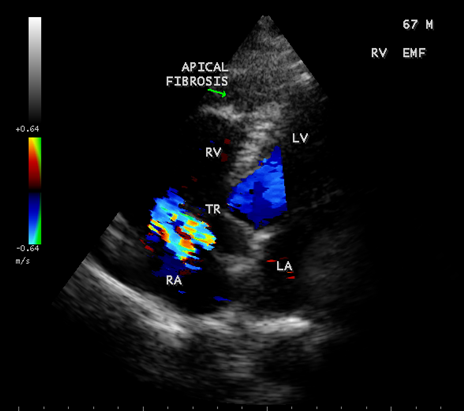

Figure 32. Endomyocardial fibrosis with aneurysmal right ventricle in a 67-year old male with RV apical fibrosis.

Figure 34: Biventricular EMF showing AV (atrioventricular) valve regurgitation in a 67- year old male.